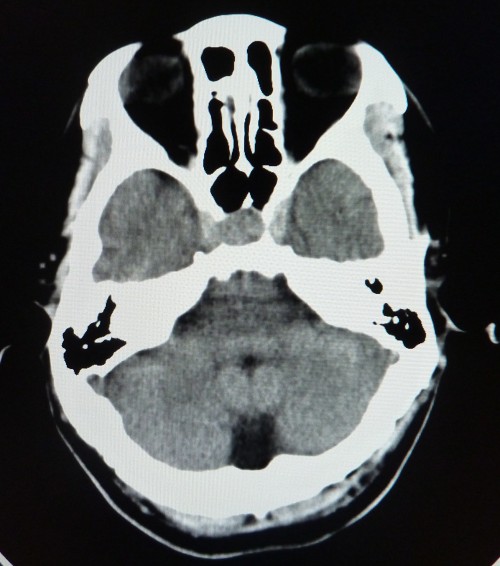

标题: CT26504:男,45岁,头痛伴呕吐两星期。 [打印本页]

标题: CT26504:男,45岁,头痛伴呕吐两星期。

鞍内可见高密度类圆形影,鞍背骨质吸收,支持垂体瘤伴出血,建议mri检查。

垂体增大,密度明显增高,考虑垂体瘤卒中,建议mr